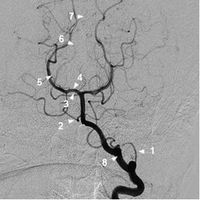

椎動脈正位2

椎動脈正位11 小腦後下動脈 2 小腦前下動脈

3 小腦上動脈 4 大腦後動脈P1段

5 大腦後動脈P2段 6 大腦後動脈P3段

7 大腦後動脈P4段 8 椎動脈

9 基底動脈

椎動脈多數起源於鎖骨下動脈,兩側椎動脈的管徑可以變化很大,一般情況下左側椎動脈管徑大於右側椎動脈管徑,但約1/4的正常人右椎動脈管徑大於左側椎動脈管徑。

基底動脈是由兩側椎動脈匯合而成,在正位片上位於中線或旁正中。基底動脈自橋延溝附近的起點到終端分為雙側大腦後動脈止,全長約32mm,平均管徑約3-4mm。分支主要有:從近端向遠端依次為小腦前下動脈、腦橋支、小腦上動脈、大腦後動脈。

大腦後動脈是基底動脈的終末。分為4段,P1段為交通前段(中腦段),為從基底動脈分叉至與後交通動脈匯合處;P2段為環池段,為從與後交通動脈匯合處至中腦後方這段距離;P3段為四疊體段,從中腦後方到距狀裂;P4段為距裂段,此段為大腦後動脈在距狀裂內的終末支。P1段在頦頂位或Towne位顯示最好,兩側P1段多不對稱,側位上P1段因從中腦前走向外側不易顯示。而P2段在側位上顯示清楚,常有一輕度向下的彎曲。兩側大腦後動脈在正位像上顯示在中腦後方彎曲向上彼此接近,標誌P3段的開始。P3段自中腦背側水平至距狀裂前僅數毫米,在Towne位或頦頂位顯示最好。P4段在正位顯示也很清楚。

小腦後下動脈供應小腦下蚓部、小腦半球下部、延髓背外側;腦橋支主要供應腦橋;小腦前下動脈主要供應小腦半球前下部、腦橋被蓋尾側部、橋臂下部、繩狀體、第四腦室脈絡叢;小腦上動脈供血小腦上蚓部、小腦半球上部小腦髓質、腦橋被蓋頭側部等。大腦後動脈皮質支主要供血大腦半球底面和內側面的一部分,中央支主要供血為丘腦、下丘腦、底丘腦、膝狀體以及中腦大部。